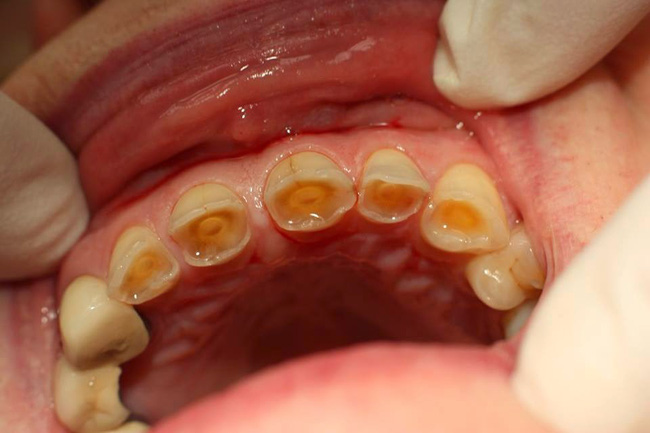

Kì thực, chúng ta có rất nhiều lầm tưởng về việc đánh răng. Cho rằng răng sau khi ăn sẽ bẩn nên phải vệ sinh ngay, nhưng đây là một thói quen cực tai hại. Lúc này, răng đang khá yếu vì tiếp xúc với axit từ thực phẩm, nếu đánh răng ngay rất dễ bào mòn men răng, khiến răng yếu, dễ ố vàng và sâu hơn nữa! Các chuyên gia răng hàm mặt khuyên bạn nên vệ sinh răng (bao gồm đánh răng hoặc súc miệng) ít nhất 30-60 phút sau khi ăn . Lúc này, độ axit đã giảm bớt và việc vệ sinh mới thật sự hiệu quả.

Men răng bị ăn mòn – hệ quả của thói quen cứ ăn xong là đánh răng ngay.